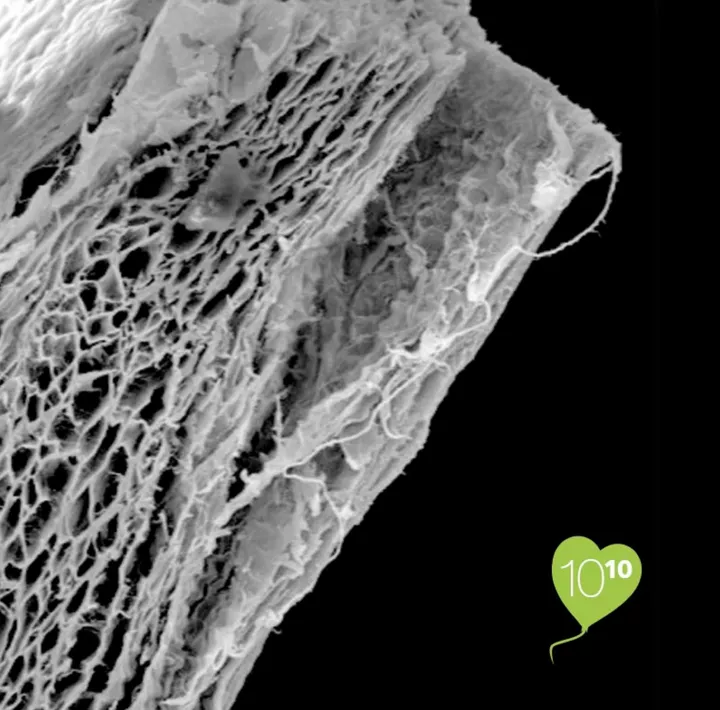

Die Jason® membrane ist eine native Kollagenmembran aus Schweineperikard, die für die Regeneration von Zahngewebe entwickelt und hergestellt wurde. Sie ist sehr dünn und bietet aufgrund der spezifischen Zusammensetzung und Struktur der perikardialen Kollagenfasern eine natürlich lange Barrierefunktion. Aufgrund der Erhaltung der natürlichen biomechanischen Eigenschaften des Perikards weist die Jason® membrane vorteilhafte Handhabungseigenschaften wie eine bemerkenswerte Reissfestigkeit und eine effektive Oberflächenanpassung auf.